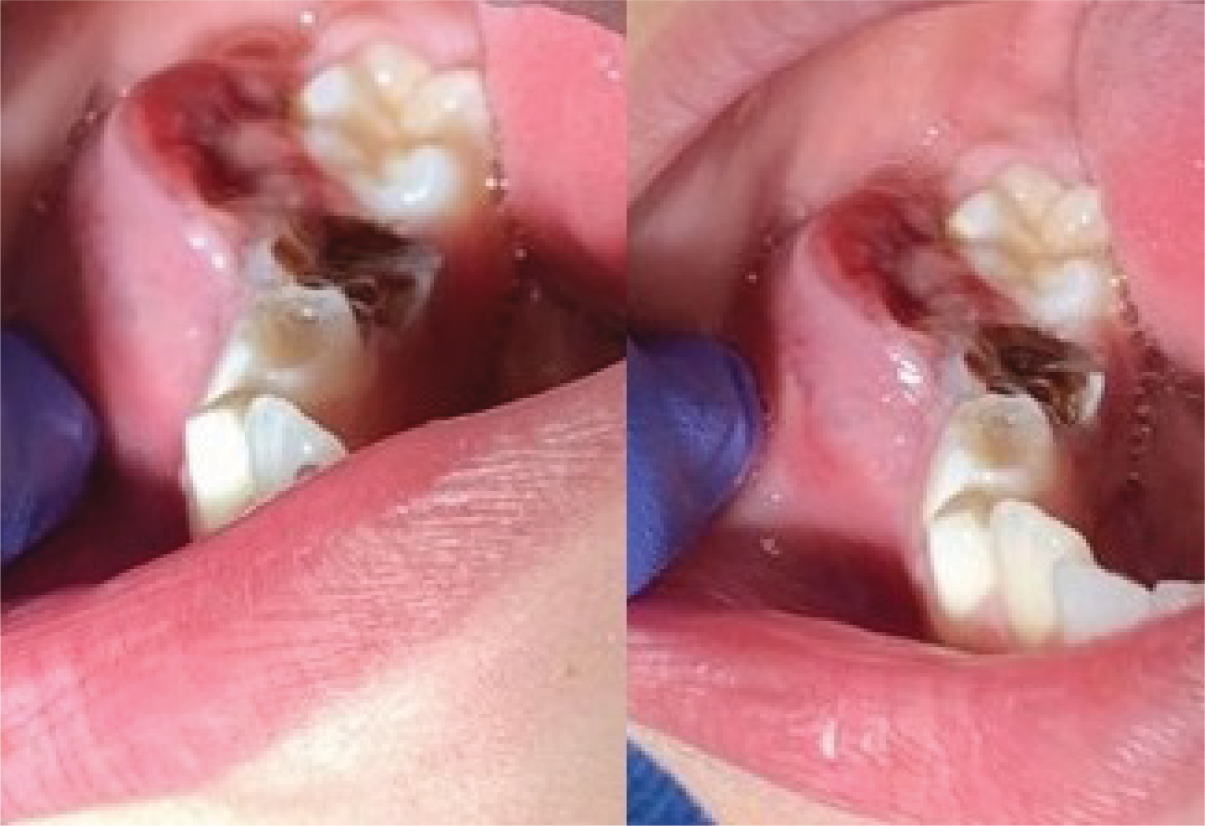

Figure 1

Intraoral view of a reddish sessile lesion in the right mandibular region.

An 8‑year‑old boy with a history of primary second molar extraction in the right mandible presented to the department of maxillofacial surgery with a painful swelling in the right lower jaw. Clinical examination revealed a reddish sessile lesion with an erythematous and ulcerated surface (Figure 1). Contrast‑enhanced computed tomography (CECT) of the right mandibular region demonstrated a non‑calcified, homogeneously enhancing solid lesion, measuring approximately 2 cm, arising from the gingiva at the outer alveolar margin (Figure 2, asterisk) and causing bulging of the buccinator muscle (Figure 2, arrowheads). Bone window reconstructions revealed superficial bone erosion (Figure 3, arrows). Histopathological examination following surgical removal confirmed the diagnosis of peripheral giant cell granuloma (PGCG).